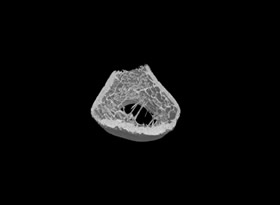

使用MicroCT可以詳細了解牙根管的三維形態(tài),測量根管的高度、體積、截面積、管壁厚度等。

1骨組織樣本掃描。

2提供2D圖、3D圖和相關參數(shù)的分析數(shù)據(jù)(骨密度BMD 單獨收費)。